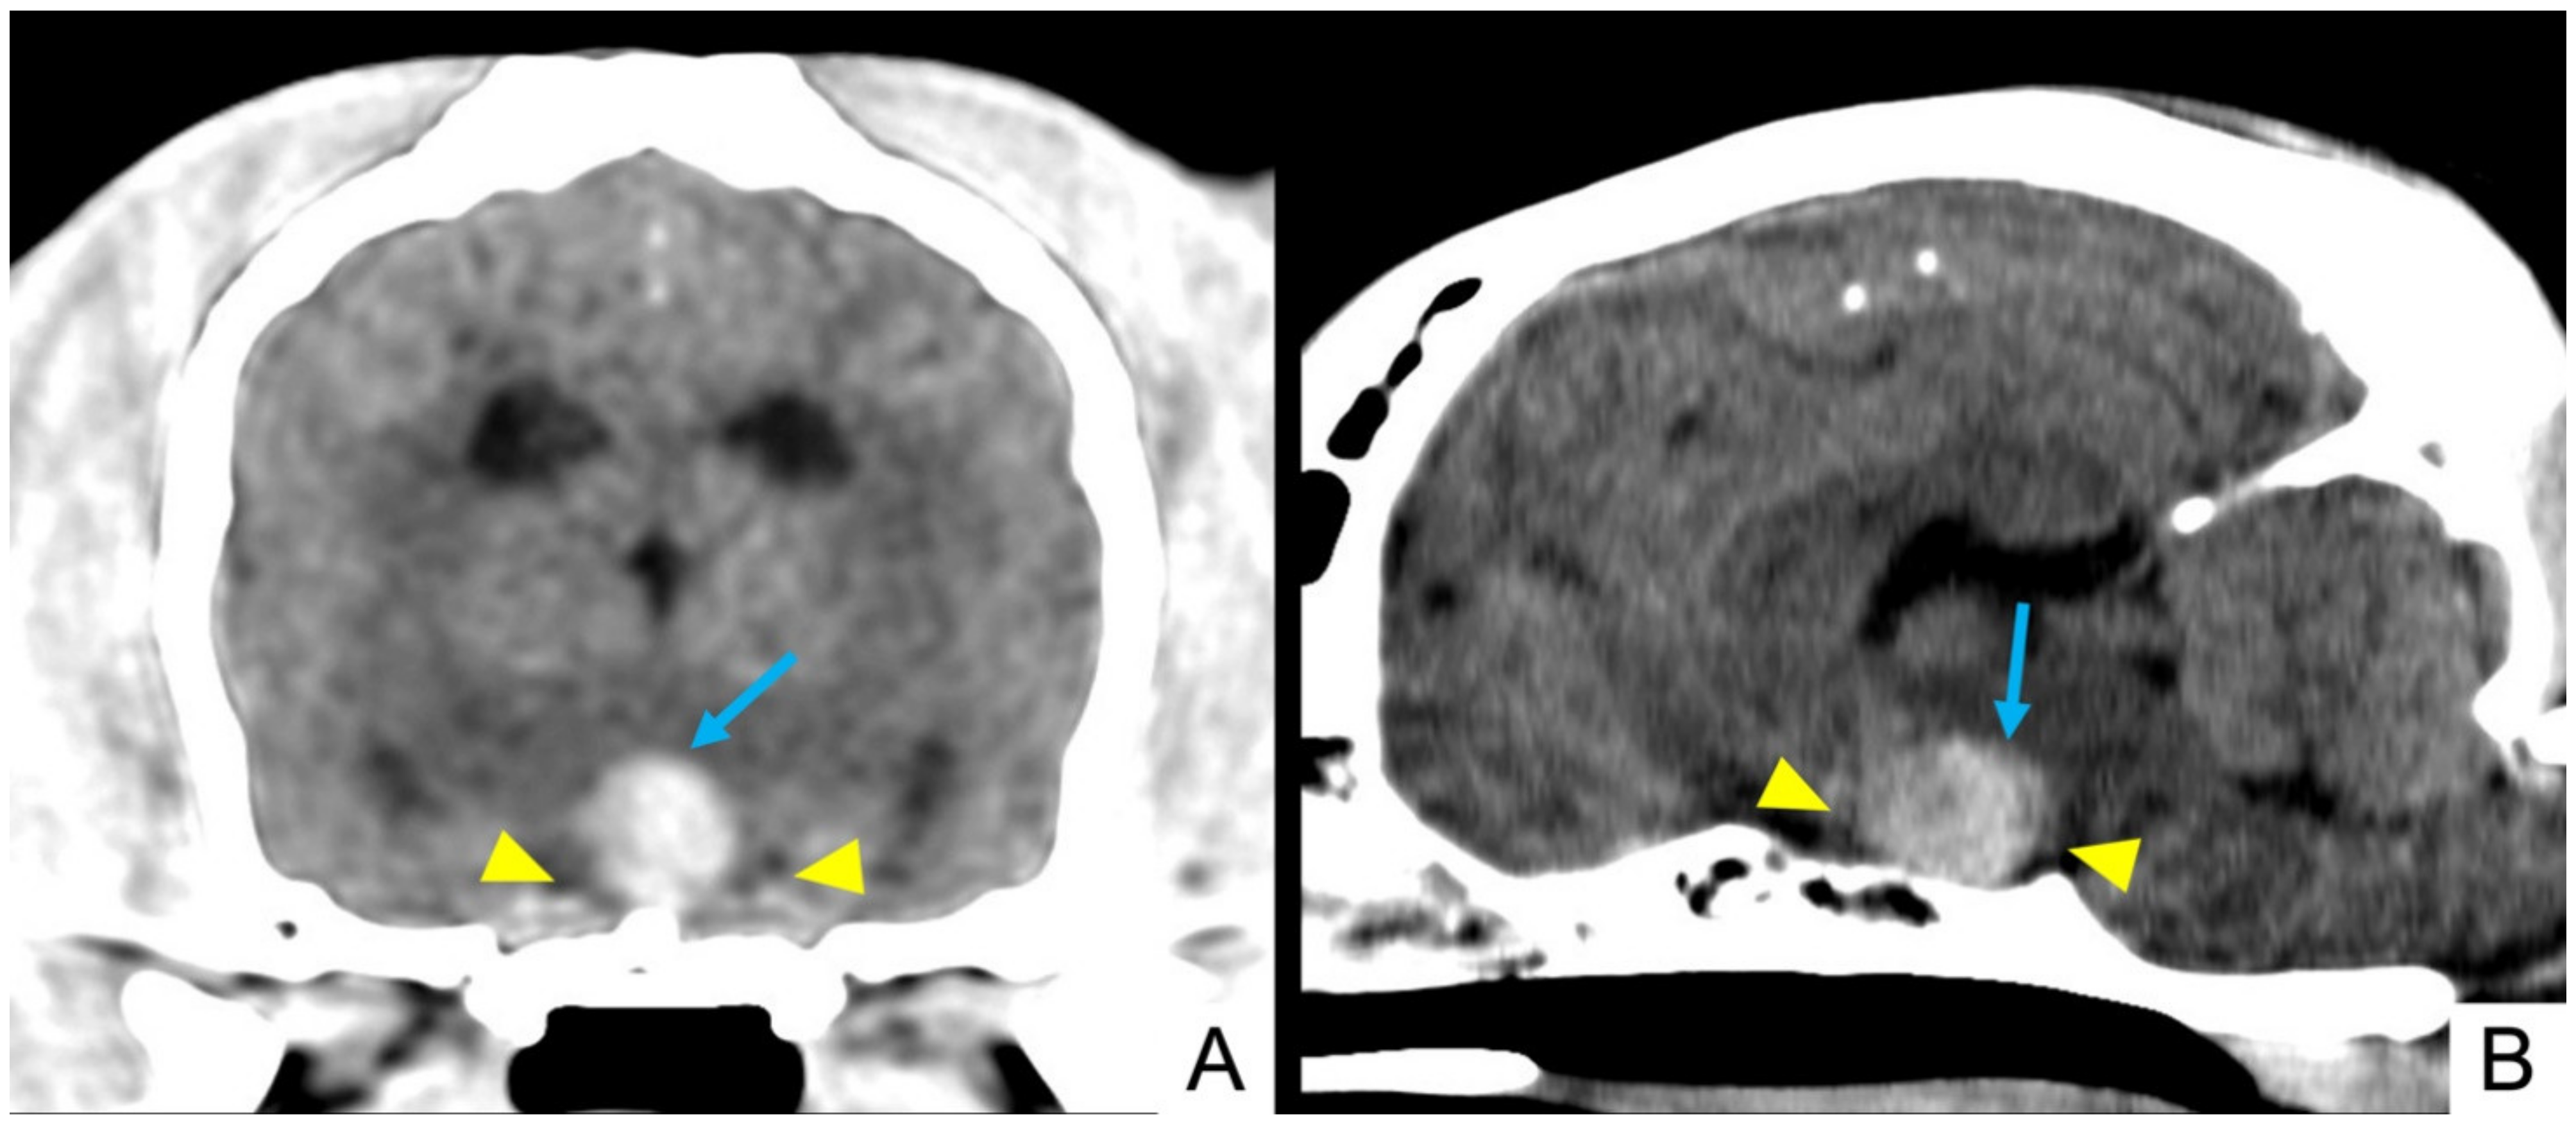

3.4. Imaging Findings

| Signalment | T1-Weighted | T2-Weighted | FLAIR | T2*/SWI | DWI | ADC | Contrast Enhancement | MRI Diagnosis |

|---|---|---|---|---|---|---|---|---|

| 1. Mixed breed MN, 9.75 y, 24.6 Kg | Homogeneous isointense | Heterogeneous isointense | Heterogeneous isointense | No | Hyperintense | Hypointense | Heterogeneous | Pituitary mass with different stages of intralesional haemorrhage |

| 2. Italian hound F, 11.5 y, 14.8 Kg | Heterogeneous isointense | Heterogeneous isointense | Heterogeneous isointense | Yes | Hyperintense | Hypointense | Heterogeneous | Pituitary mass with intralesional haemorrhage |

| 5. Mixed breed FN, 12.7 y, 30 Kg | Homogeneous isointense | Heterogeneous isointense | Heterogeneous isointense | Yes | Isointense | Isointense | Heterogeneous | Pituitary mass with intralesional haemorrhage |

| 6. Beagle FN, 7.6 y, 16.6 Kg | Heterogeneous hypointense | Heterogeneous hyperintense | Heterogeneous hyperintense | Yes | Hypointense | Hypointense | Heterogeneous | Pituitary mass with intralesional haemorrhage |

| 7. Labrador Retriever F, 5 y, 31.2 Kg | Heterogeneous hypointense | Heterogeneous hyperintense | Heterogeneous hyperintense | \ | Hypointense | Hyperintense | Heterogeneous | Pituitary mass with intralesional haemorrhage |

| 8. Labrador Retriever FN, 10.8 y, 35 Kg | Heterogeneous hypointense | Heterogeneous hyperintense | Heterogeneous hyperintense | No | \ | \ | Heterogeneous | Pituitary mass |

| 9. Mixed breed FN, 5.8 y, 21 Kg | Heterogeneous hypointense | Heterogeneous hyperintense | Heterogeneous hyperintense | Yes | \ | \ | Heterogeneous | Pituitary mass with intralesional haemorrhage |

| 11. Boxer FN, 11.4 y, 27.4 Kg | Homogeneous hyperintense | Heterogeneous hyperintense | Heterogeneous hyperintense | \ | \ | \ | Heterogeneous | Pituitary mass with intralesional haemorrhage |

| 12. Springer Spaniel M, 13.7 y, 18.7 Kg | Heterogeneous isointense | Heterogeneous hyperintense | Heterogeneous hyperintense | Yes | Hypointense | Hyperintense | Heterogeneous | Pituitary mass with intralesional haemorrhage |